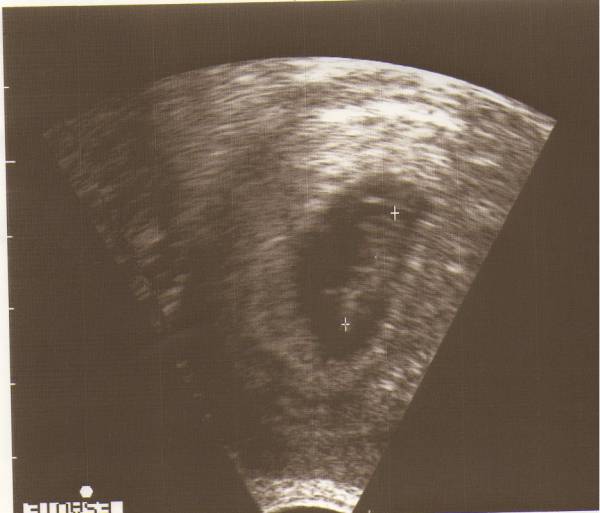

Tegnapi két kép:

Kép

Adatok pedig:

a petezsák 47mm

a baba 19mm

Óriás bébi :lol:

Upsz,az első fejjel lefelé sikerült :oops:

A javított változat! :oops: :oops: :oops: :oops: :oops: